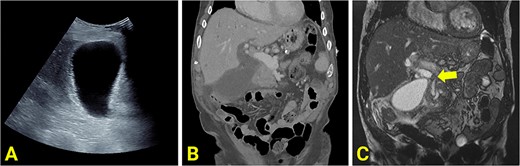

Bloods on admission revealed the following: haemoglobin (Hb) 141 (130–180 g/L), white cell count (WCC) 23.7 (4–11 × 109/L), bilirubin total/direct 35/25 (<20/<7 μmol/L), alkaline phosphatase (ALP) 383 (30–110 U/L), gamma-glutamyl transferase (GGT) 267 (<55 U/L), alanine transaminase (ALT) 738 (<35 U/L), and aspartate aminotransferase (AST): 884 (<40 U/L). Initial imaging suggested acute cholecystitis; ultrasound (US) showed a distended gallbladder with a thickened wall (Fig. 1A), and non-contrast computed tomography (CT) showed a distended gallbladder with pericholecystic stranding (Fig. 1B). One day later, magnetic resonance cholangiopancreatography (MRCP) showed cholecystitis, biliary duct dilatation, and choledocholithiasis (Fig. 1C). No cholelithiasis was present. Blood cultures were positive for Escherichia coli.

(A) Ultrasound scan showing a distended and enlarged gallbladder with a thickened wall suggestive of acute cholecystitis. No obvious gallstones are present. (B) Reconstructed contrast-enhanced coronal CT shows an enlarged and distended gallbladder, a thickened gallbladder wall, pericholecystic fluid, and a dilated common hepatic duct. (C) MRCP showing an obstructed gallstone at the confluence of the common hepatic duct, common bile duct and cystic duct (marked with arrow).